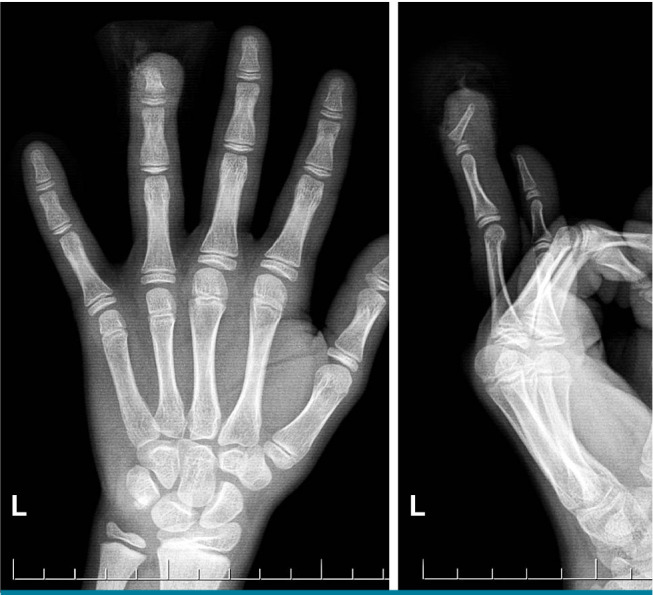

{"title":"The silent threat under the nail: Evaluation of Seymour fractures in pediatric patients.","authors":"Ahmet Yiğitbay, Gökhan Yıldırım, Muhammed Can Ari, Hakan Çetin, Cemal Kural","doi":"10.52312/jdrs.2025.2066","DOIUrl":null,"url":null,"abstract":"<p><strong>Objectives: </strong>This study aims to examine the diagnosis, treatment methods, and outcomes of Seymour fractures and to address diagnostic challenges in these fractures.</p><p><strong>Patients and methods: </strong>Between January 2020 and November 2023, a total of 28 pediatric patients (18 males, 11 females; mean age: 6.8±4.5 years; range, 1 to 15 years) who presented with Seymour fractures within 24 h of injury were retrospectively analyzed. Patients were treated either conservatively in the emergency department or surgically in the operating room if closed reduction was unsuccessful. All patients received intravenous antibiotics within the first 24 h, followed by oral antibiotics after discharge. Infection rates, physeal arrest, and nail dystrophy were evaluated during follow-up.</p><p><strong>Results: </strong>The mean follow-up was 16.6±6.6 (range, 12 to 32) months. There was no statistically significant difference in the affected side (right/left) and fingers (p=0.43 and p>0.05, respectively). The complication rate was significantly higher in surgically treated patients compared to those treated conservatively (p=0.02 and p<0.05, respectively). Evaluation of patients based on finger mobility showed no motion loss in the conservatively treated group at the final follow-up. In the surgically treated group, however, motion restrictions were noted in only two patients. Early antibiotic administration within 24 h significantly reduced infection rates, with only 3.5% (n=1) of patients developing osteomyelitis.</p><p><strong>Conclusion: </strong>Stable Seymour fractures can be treated conservatively in the emergency setting, while complex cases may require surgical intervention in the operating room. Early antibiotic use is essential in minimizing infection risk. Antibiotherapy within the first 24 h after injury is an effective way to prevent infection.</p>","PeriodicalId":73560,"journal":{"name":"Joint diseases and related surgery","volume":"36 2","pages":"320-327"},"PeriodicalIF":1.9000,"publicationDate":"2025-04-05","publicationTypes":"Journal Article","fieldsOfStudy":null,"isOpenAccess":false,"openAccessPdf":"https://www.ncbi.nlm.nih.gov/pmc/articles/PMC12086482/pdf/","citationCount":"0","resultStr":null,"platform":"Semanticscholar","paperid":null,"PeriodicalName":"Joint diseases and related surgery","FirstCategoryId":"1085","ListUrlMain":"https://doi.org/10.52312/jdrs.2025.2066","RegionNum":0,"RegionCategory":null,"ArticlePicture":[],"TitleCN":null,"AbstractTextCN":null,"PMCID":null,"EPubDate":"","PubModel":"","JCR":"Q2","JCRName":"ORTHOPEDICS","Score":null,"Total":0}

Patients and methods: Between January 2020 and November 2023, a total of 28 pediatric patients (18 males, 11 females; mean age: 6.8±4.5 years; range, 1 to 15 years) who presented with Seymour fractures within 24 h of injury were retrospectively analyzed. Patients were treated either conservatively in the emergency department or surgically in the operating room if closed reduction was unsuccessful. All patients received intravenous antibiotics within the first 24 h, followed by oral antibiotics after discharge. Infection rates, physeal arrest, and nail dystrophy were evaluated during follow-up.

Results: The mean follow-up was 16.6±6.6 (range, 12 to 32) months. There was no statistically significant difference in the affected side (right/left) and fingers (p=0.43 and p>0.05, respectively). The complication rate was significantly higher in surgically treated patients compared to those treated conservatively (p=0.02 and p<0.05, respectively). Evaluation of patients based on finger mobility showed no motion loss in the conservatively treated group at the final follow-up. In the surgically treated group, however, motion restrictions were noted in only two patients. Early antibiotic administration within 24 h significantly reduced infection rates, with only 3.5% (n=1) of patients developing osteomyelitis.

Conclusion: Stable Seymour fractures can be treated conservatively in the emergency setting, while complex cases may require surgical intervention in the operating room. Early antibiotic use is essential in minimizing infection risk. Antibiotherapy within the first 24 h after injury is an effective way to prevent infection.